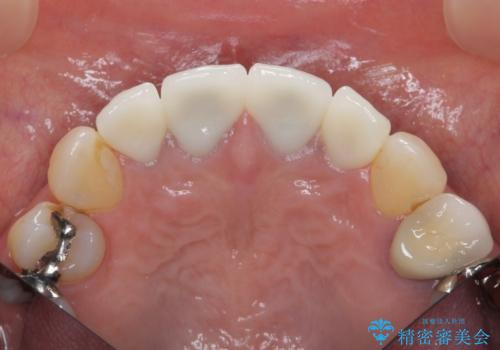

前歯をきれいにしたい

- 「黒ずみの前立つ前歯をやりかえ、きれいにしたい。」と希望され来院されました。

金属色の目立つ前装冠を除去し、発生していた小さな虫歯を丁寧に全て除去しジルコニアセラミッククラウンで審美的な前歯となるような治療を計画します。

- 44万円(仮歯・ジルコニアクラウン×4)費用は治療当時の料金となります

金属を用いないジルコニアセラミッククラウンは透明感の再現性に優れ、審美性と自然な仕上がりの両立を期待することができます。